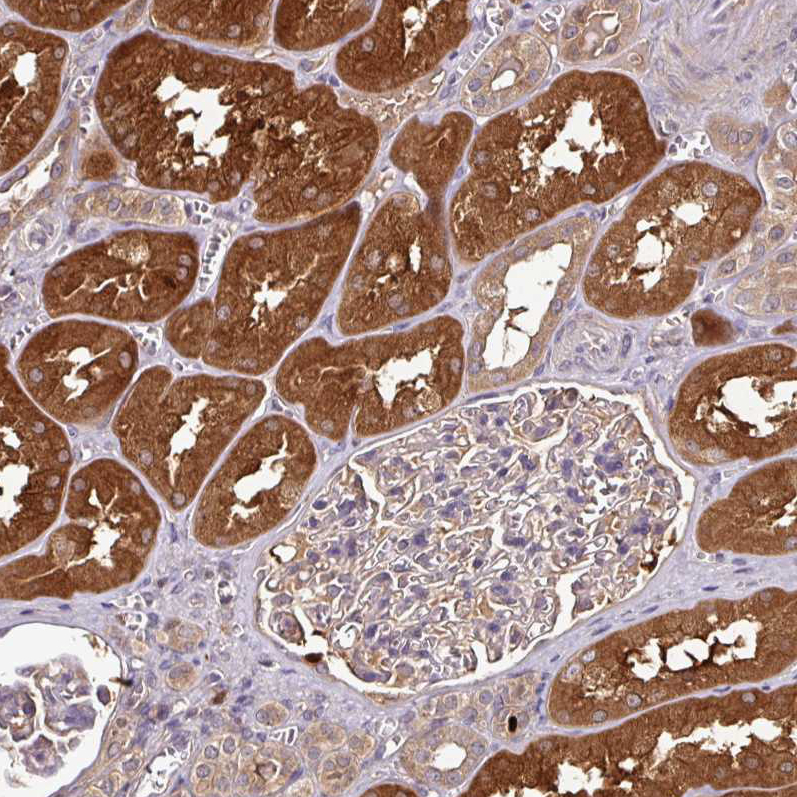

Immunohistochemical staining of human kidney shows strong cytoplasmic positivity in cells in tubules.